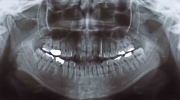

初診時

マルチブラケット終了時